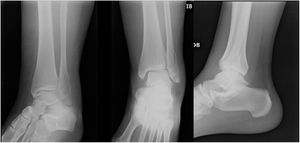

Materiales y MétodosSe realizó un ensayo auto-controlado, aleatorizado, doble ciego, multicéntrico, mediante la aplicación de encuestas en tres países a ortopedistas generales, subespecialistas en cirugía de pie y tobillo y residentes de ortopedia y traumatología. Se estableció el criterio de aleatorización simple mediante la presencia de los encuestados en los simposios de pie y tobillo en la ciudad de Guayaquil en el marco del congreso Ecuatoriano de Ortopedia y Traumatología, En la ciudad de Cali en el marco del curso nacional del Pie y Tobillo de la sociedad Colombiana de Cirugía Ortopédica y Traumatología y en la ciudad de Cancún en el marco del Congreso mexicano de Ortopedia y Traumatología de la FEMECOT, estableciéndose como criterio de inclusión estar en disposición de evaluar los casos clínicos y realizar la encuesta independientemente de su grado de entrenamiento o años de experiencia. Se entregaron cuatro casos de fracturas de tobillo Webber B de características quirúrgicas por sus mediciones radiológicas con desenlaces conocidos por los autores Senior (Eduardo Reina, Juan Manuel Herrera, Carlos Ramirez, Bosco Mendoza y Victor Toledo) como se observa en la figura 1.

En el caso número 1 se estableció como criterio quirúrgico la diferencia de el ángulo talocrural de 6° y la línea de shenton con una incongruencia de 3mm en el lado fracturado figuras 2 y 3